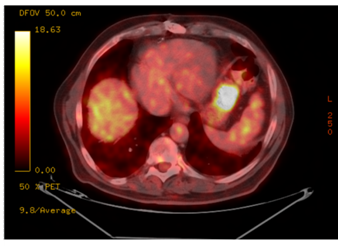

A 76year old man was admitted due to upper gastrointestinal bleeding. He was hemodynamically stable. Physical examination was unremarkable except for melena on rectal examination. Nasogastric tube showed clear gastric content. There was no history of recent abdominal pain, weight lost or vomiting. On admission hemoglobin level was 8.9g/dl. All other blood tests including coagulation profile were normal. After initial resuscitation, he underwent urgent Gastroscopy in which a sub mucosal 3cm ulcerated mass was identified at the greater curvature without evidence of active bleeding. Bleeding ceased spontaneously. Further evaluation was performed. Endoscopic ultra sound showed a 3cm mixed echogenicity mass arising from the sub mucosa without lymphadenopathy. Biopsies were not taken. An abdominal computer tomography confirmed the diagnosis of a 3cm sub mucosal lesion with peripheral enhancement after injection of contrast material. PET CT showed a pathological uptake of FDG in the gastric tumor only (Figure 1) and a preoperative diagnosis of GIST were made.

Figure 1 PET CT showed a pathological uptake of FDG in the gastric tumor.